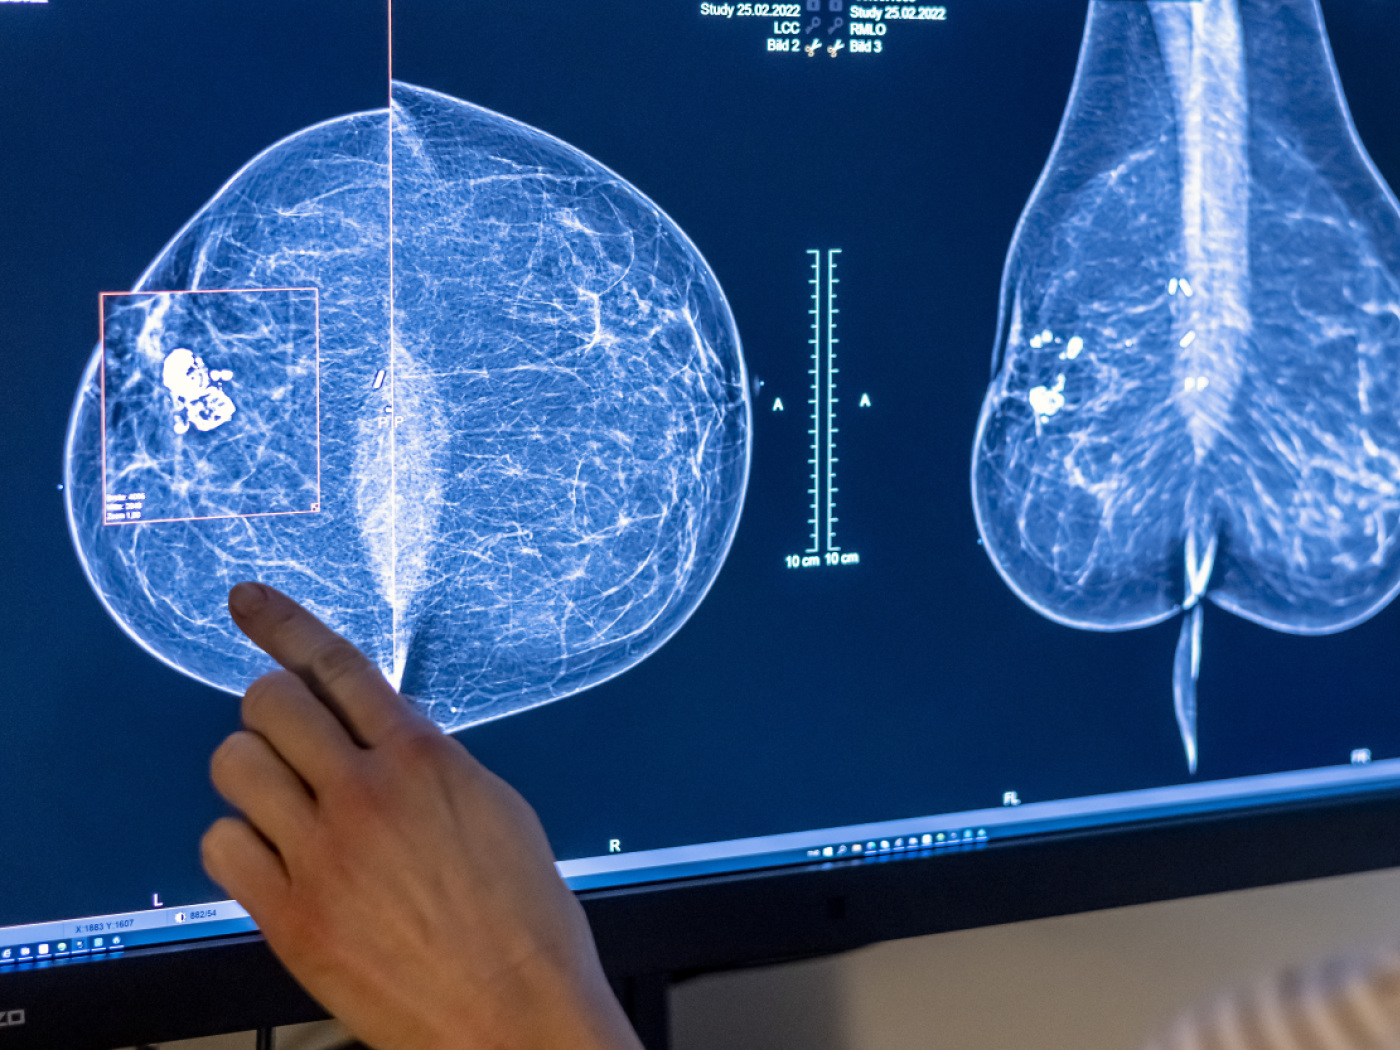

Eine winzige Abweichung im Erbgut kann teure Krebsmedikamente nutzlos machen. Wie Forschende der Universität Basel in einer neuen Studie zeigen, können schon kleinste genetische Unterschiede die Wirksamkeit von Antikörper-Therapien aufheben.

(Keystone-SDA) Dies, indem sie die Bindung der Medikamente an ihr Ziel verhindern, wie eine am Mittwochabend in der Fachzeitschrift «Science Translational Medicine» erschienene Studie zeigt. Die Wissenschaftlerinnen und Wissenschaftler sehen in ihrer Entdeckung eine mögliche Erklärung, warum manche Patientinnen und Patienten nicht auf eine Antikörper-Therapie ansprechen.

Bei vielen Erkrankungen kommen Therapien auf Basis von Antikörpern zum Einsatz. Antikörper erkennen ganz spezifische Strukturen und binden daran. So können sie beispielsweise Wirkstoffe an genau die richtige Zielstruktur im Körper heranführen.